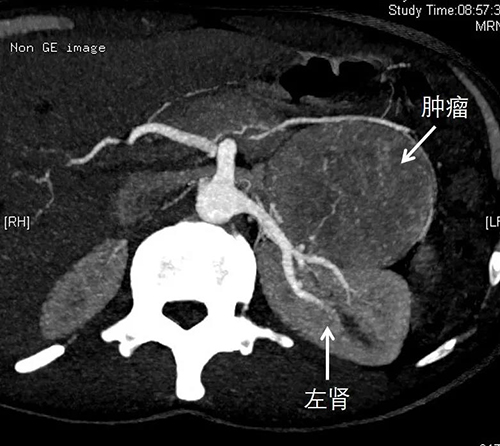

患者嗜铬细胞瘤CT图像

家住高密的马先生,年仅30岁,近半年来无明显原因多次出现突发性头痛、胸闷、伴发作性大汗淋漓及四肢乏力症状,症状发作时患者血压急剧升高,最高曾达250/145mmHg,近1月来发作越发频繁,每日发作1-2次以上。2周前,患者于单位突发头晕,视物模糊、心慌。晕倒15分钟后被同事发现紧急送往当地医院。当地医院检查发现患者腹膜后巨大占位,遂转我院进一步治疗。入院后,经泌尿外科专家检查,患者左侧腹膜后一直径约10cm肿瘤,活性极强,严重压迫周围血管脏器,如同一枚“炸弹”,阵发性高血压危象频繁发作,随时可能危及生命。